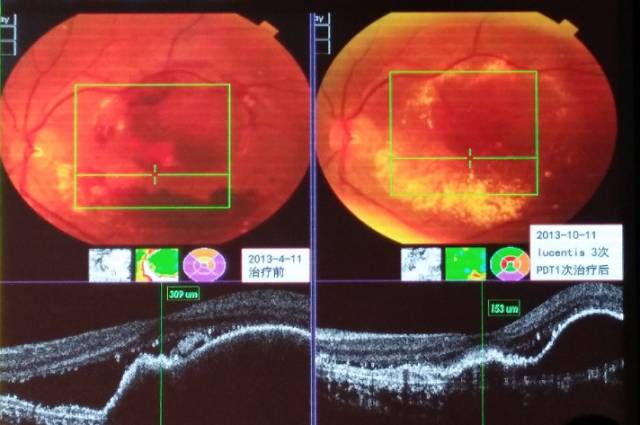

利器三:光动力疗法(photodynamic therapy, PDT)

光动力疗法是在光敏剂的引导下,通过一种特殊的非热能激光照射,破坏黄斑部异常的新生血管,从而减少黄斑区病变组织的出血、水肿和渗出,稳定患者视力,提高患者生活质量,是一种目前国内外公认的治疗黄斑脉络膜新生血管(CNV)的安全有效微创的新技术。PDT主要用于治疗湿性黄斑变性、病理性近视合并黄斑病变、中心性渗出性视网膜病变、中心性浆液性视网膜脉络膜病变等黄斑部新生血管疾病。对于某些对抗VEGF药物治疗反应迟缓或者耐受的CNV患者,可联合或者更改为PDT治疗,往往会取得一些令人满意的治疗效果(见图12)。

图12. 息肉样脉络膜血管病变抗VEGF联合PDT治疗前后眼底和OCT对比图